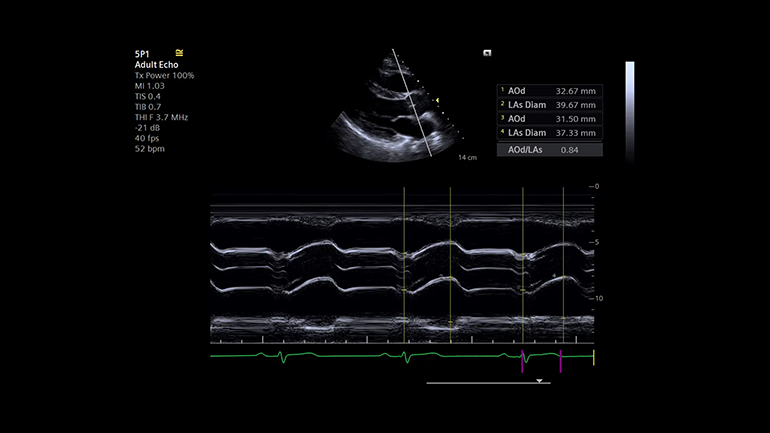

Визуализация

Предоставление высококачественной медицинской помощи подразумевает возможность сканирования практически любых пациентов независимо от их телосложения, веса или состояния. Благодаря своей клинической универсальности в сочетании с ведущей технологией эластографии УЗ-система ACUSON Juniper позволяет расширить спектр ультразвуковых исследования практически для всех категорий пациентов и диагностических ситуаций.

B-режим. Высокое контрастное разрешение и однородность изображений — отличное диагностическое качество.

B-режим. Высокое контрастное разрешение и однородность изображений — отличное диагностическое качество. Цветовые допплеровские режимы. Надежность диагностики повышается благодаря высокочувствительному цветовому доплеровскому режиму при снижении артефактов яркости цвета.

Цветовые допплеровские режимы. Надежность диагностики повышается благодаря высокочувствительному цветовому доплеровскому режиму при снижении артефактов яркости цвета.Специализированные опциональные приложения

Стресс-эхокардиография. Функция стресс-эхокардиографии включает в себя комплекс инструментов и измерений для получения данных о циклах сердечной деятельности на различных этапах стресс-эхокардиографического исследования, просмотра, выборочного сравнения, оценки и архивирования наборов кинопетель с ЭКГ-синхронизацией.

Стресс-эхокардиография. Функция стресс-эхокардиографии включает в себя комплекс инструментов и измерений для получения данных о циклах сердечной деятельности на различных этапах стресс-эхокардиографического исследования, просмотра, выборочного сравнения, оценки и архивирования наборов кинопетель с ЭКГ-синхронизацией. Технология оценки скорости распространения поперечной волны и эластичности в выбранной области интереса (Virtual Touch quantification). Метод измерения скорости поперечных (сдвиговых волн) в режиме реального времени, в котором используются низкочастотные акустические импульсы (ARFI), генерируемые непосредственно ультразвуковым датчиком. Оценка скоростей сдвиговых волн в выбранной врачом зоне интереса коррелирует с показателями жесткости ткани.

Технология выполнения измерений левых отделов сердца (eSie Left Heart). Пакет измерений левых отделов сердца eSie Left Heart — это надежный инструмент, который повышает надежность и оптимизирует рабочий процесс благодаря автоматическому определению границ левого желудочка и левого предсердия и выполнению измерений при стандартных трансторакальных исследованиях у взрослых пациентов.

Технология выполнения измерений левых отделов сердца (eSie Left Heart). Пакет измерений левых отделов сердца eSie Left Heart — это надежный инструмент, который повышает надежность и оптимизирует рабочий процесс благодаря автоматическому определению границ левого желудочка и левого предсердия и выполнению измерений при стандартных трансторакальных исследованиях у взрослых пациентов. Технология автоматического исследования фолликулов (syngo ® Auto Follicle). В технологии syngo ® Auto Follicle реализован автоматический метод измерений, обеспечивающий быструю и точную оценку фолликулов. Автоматическое выполнение измерений и запись результатов помогают сократить продолжительность исследования.

Технология автоматического исследования фолликулов (syngo ® Auto Follicle). В технологии syngo ® Auto Follicle реализован автоматический метод измерений, обеспечивающий быструю и точную оценку фолликулов. Автоматическое выполнение измерений и запись результатов помогают сократить продолжительность исследования. Автоматизация процесса измерений (eSie Measure). Технологя eSie Measure предназначена для ускорения рабочего процесса благодаря полуавтоматическому выполнению измерений при стандартных эхокардиографических исследованиях, например. Это повышает эффективность работы и согласованность результатов для врачей-диагностов.

Автоматизация процесса измерений (eSie Measure). Технологя eSie Measure предназначена для ускорения рабочего процесса благодаря полуавтоматическому выполнению измерений при стандартных эхокардиографических исследованиях, например. Это повышает эффективность работы и согласованность результатов для врачей-диагностов. Технология автоматического измерения основных биометрических показателей плода (syngo ® Auto OB). syngo ® Auto OB реализован инновационный алгоритм распознавания анатомических ориентиров для шести стандартных измерений плода: CRL — копчико-теменной размер, BPD — бипариетальный размер головы, HL — длина плечевой кости, HC — окружность головы, AC — окружность живота и FL — длина бедренной кости. Благодаря этому все перечисленные измерения можно выполнить автоматически, одним нажатием функциональной кнопки.